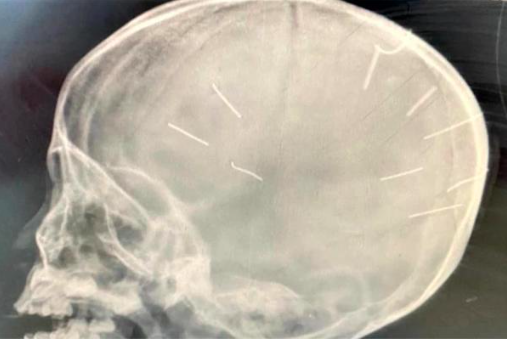

Sau khi các bác sĩ tiếp nhận bệnh nhân, tiến hành đặt ống, chụp phim đã phát hiện 9 chiếc đinh trên phim chụp có hình ảnh cản quang trên hộp sọ. Trong quá trình kiểm tra, thăm khám, các bác sĩ phát hiện cánh tay phải của bé đã được bó bột trong 2 tuần.